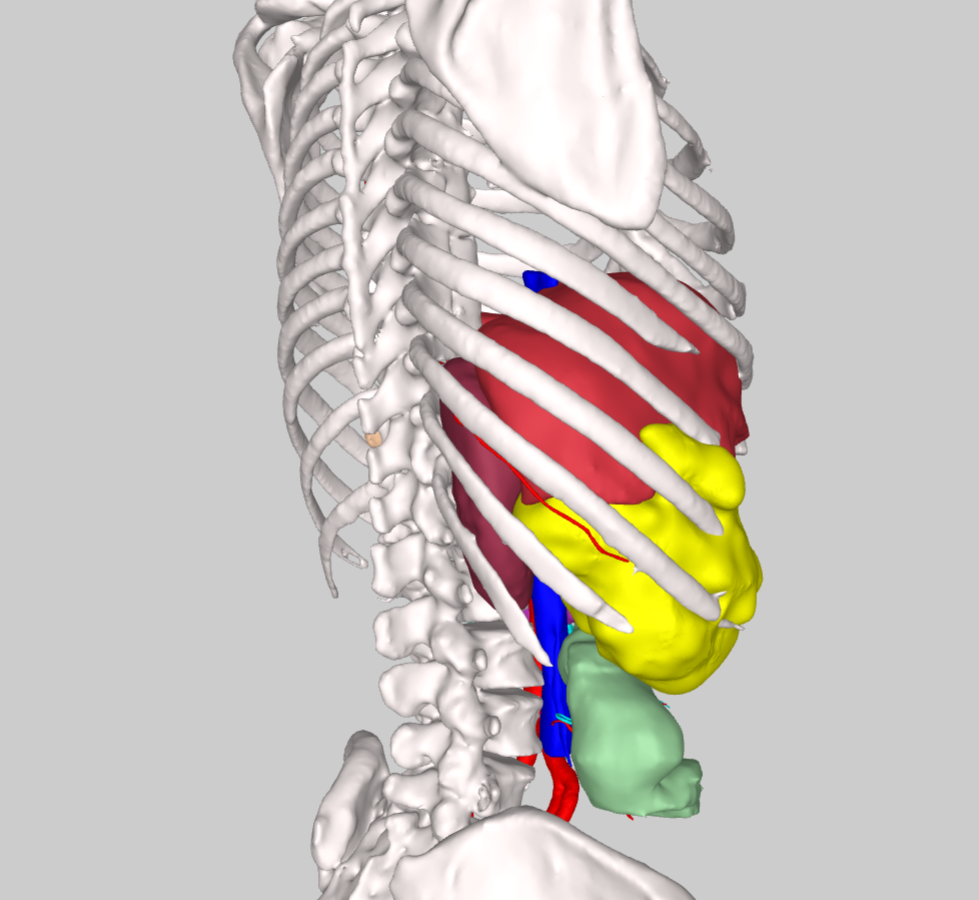

术前CT评估肿物与周围脏器关系,横截面与冠状面

影像检查显示,肿物起源于第7,8肋骨,沿胸腹壁蔓延累及第7至第11肋,上界与肝脏S5、S6段分界不清,内侧包膜紧贴右侧结肠,后方逼近右肾。“患者首次手术已切除部分肋骨,此次复发范围更广、侵袭更深,既要确保肿瘤完整切除(R0切除),又要最大限度保护重要脏器,需要多学科专家协作和新技术手段保驾护航。”骨科王伟东副主任在初次讨论时指出了本案例的关键节点。